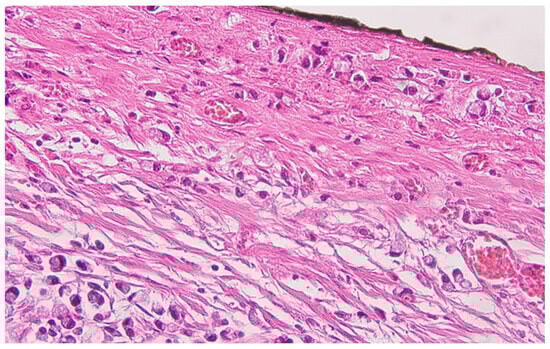

Collision Tumors of the Colon and Peritoneum: Signet-Ring Cell Carcinoma and Granular Cell Tumor

2. Case Report

Histopathological Findings